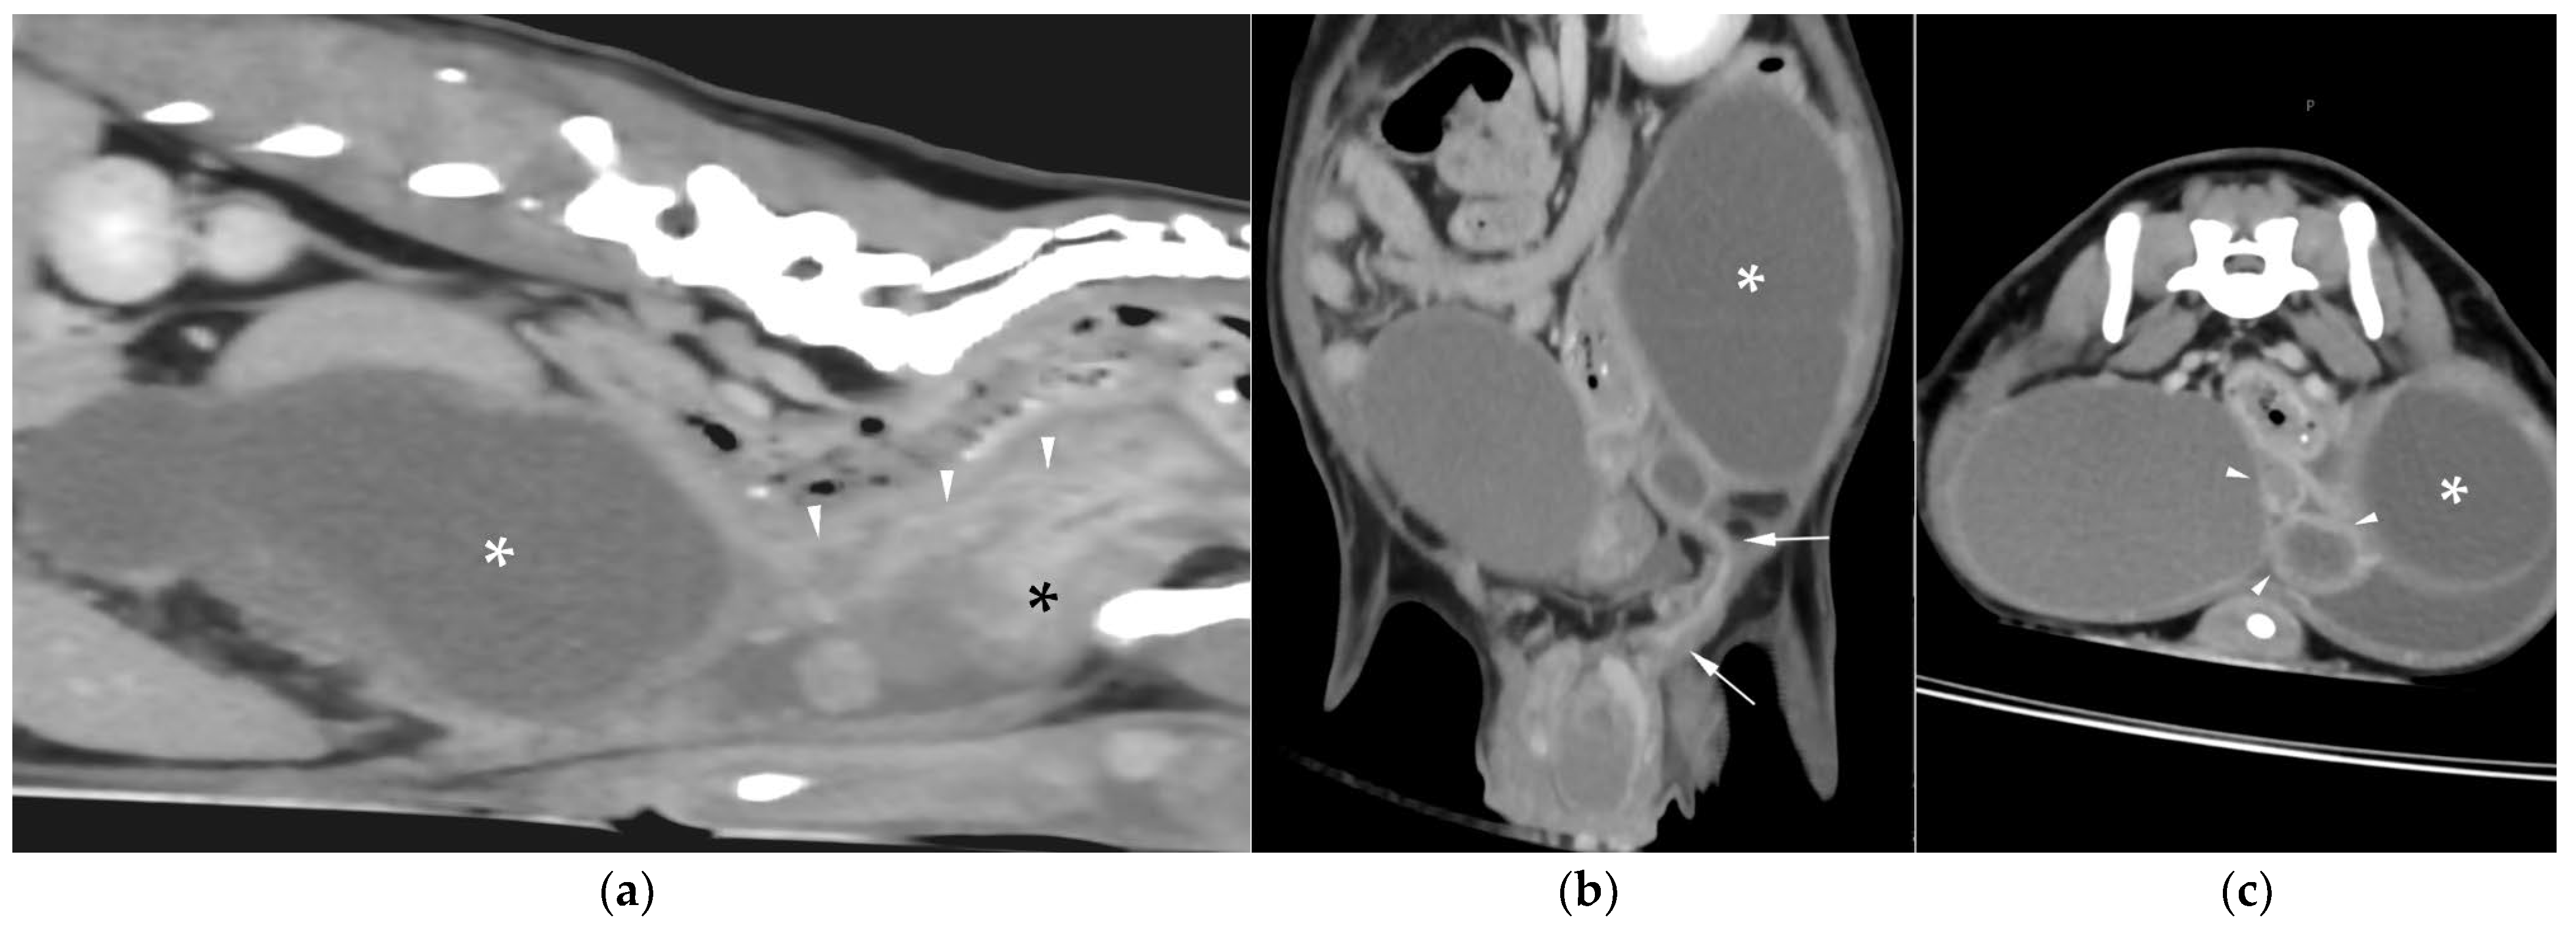

AUS in all three dogs revealed a fluid-filled cavitary structure originating in the caudal peritoneum between the colon and urinary bladder and extending cranially through the mid-abdomen, causing a mass effect. In cases 1 and 2, the lesion continued bilaterally as paired, thin tubular extensions coursing caudally through the inguinal rings adjacent to each testis (Figure 1a). In case 1, a focal mural narrowing resembling a uterine cervix was noted caudally (Figure 1b). The wall was thin and smooth in case 1, while in case 2 it was irregular, especially in its caudal aspect (Figure 2a,b). No information was available regarding the course of the UM horns or wall appearance for case 3. The luminal content consisted of echogenic, inhomogeneous fluid in all cases (Figure 3a); in case 2, sedimentation created fluid–fluid levels (Figure 3b).

In cases 1 and 2, both testes were scrotal, with multiple bilateral nodules in case 1 and a single nodule in the left testis in case 2. Case 3, previously orchiectomized on the left side, presented with a large, heterogeneous right-sided cranial abdominal mass.

Additional findings in all dogs included: enlarged, heterogeneous, cystic prostate; echogenic sediment in the urinary bladder; free peritoneal fluid [moderate and echogenic in case 2 (Figure 2a); mild and anechoic in cases 1 and 3]; and bilateral medial iliac lymphadenomegaly (moderate in cases 2 and 3; mild in case 1).

Figure 1. Abdominal ultrasound (AUS) of case 1: (a) Oblique view of a uterine horn (arrowheads) within the scrotum, with the testis in the center (asterisk) and the epididymis on the right side of the image; (b) Longitudinal view of the caudal aspect of the uterus masculinus (UM) showing a focal cervix-like mural narrowing ventral to the descending colon (arrows).